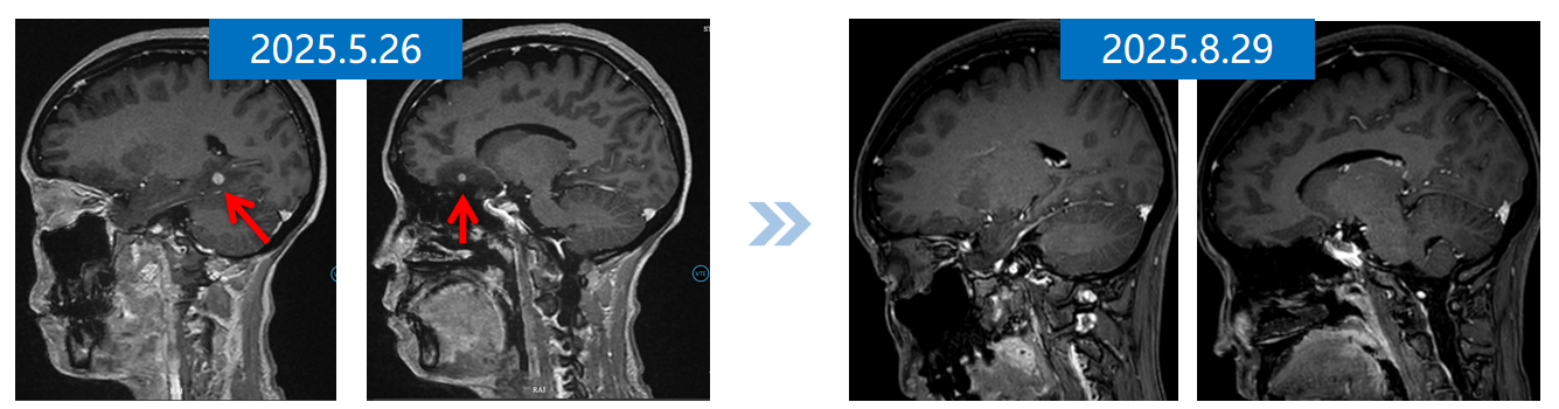

2025年5月26日,颅内MRI示颅内病灶进展。

图片111.png

一线治疗前后颅内MRI

2025年8月29日复查颅脑MRI,显示右侧颞枕部转移灶消失,颅内疗效评估为完全缓解(CR)

5.png

二线治疗前后颅内MRI